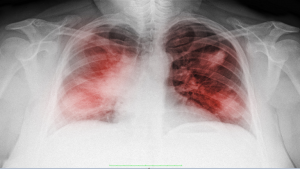

دراسة جديدة تفسر سبب انخفاض مستويات الأكسجين لدى مرضى “كوفيد-19”

ألقت دراسة جديدة الضوء على سبب معاناة العديد من مرضى “كوفيد-19″، حتى أولئك الذين ليسوا في المستشفى، من نقص الأكسجة.

وتُظهر الدراسة، التي نُشرت في مجلة Stem Cell Reports، وأجراها باحثون من جامعة ألبرتا، أيضا، سبب كون عقار ديكساميثازون المضاد للالتهابات علاجا فعالا لأولئك المصابين بالفيروس.